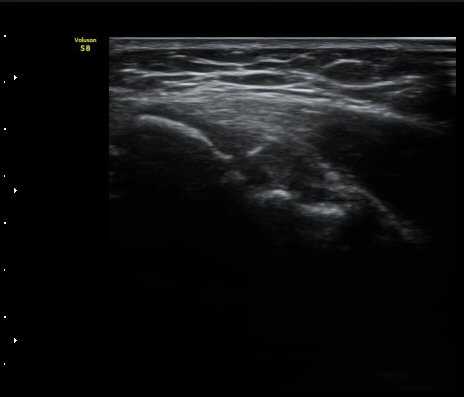

³»»ó°ú Á¾´Ü¸é°Ë»ç»ó  ³»ÃøºÎÀδë Àú¿¡ÄÚ ºÎÁ¾°ú ³»»ó°ú ÀÎ´ë ºÎÂøºÎ ÇÇÁú°ñÀÇ ºÒ±ÔÄ¢º¯È­¿Í

°ñÆíÀÌ °üÂûµÇ°í(±×¸² 1, 2, 3, 4) ÀÌ·±¼Ò°ßÀº °ÇÃø°ú ºñ±³ÇÏ¸é ´õ¿í ¶Ñ·ÈÇÔ(±×¸² 5, 6).